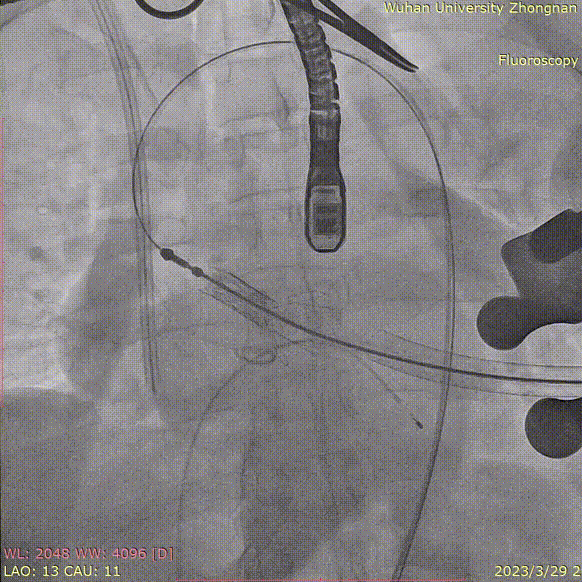

术中造影角度LAO 13°,CAU 11°;主动脉弓、降主动脉及双侧髂总动脉散在钙化,主动脉弓、腹主动脉局部管壁增厚,腹主动脉局部管壁不规则;升主动脉夹层、窦管交界增宽。

患者前降支中段重度狭窄,充分预扩后置入3.5*19mm支架一枚,复查造影提示支架膨胀良好,无明显残余狭窄。

猪尾放置于无冠窦行根部造影: